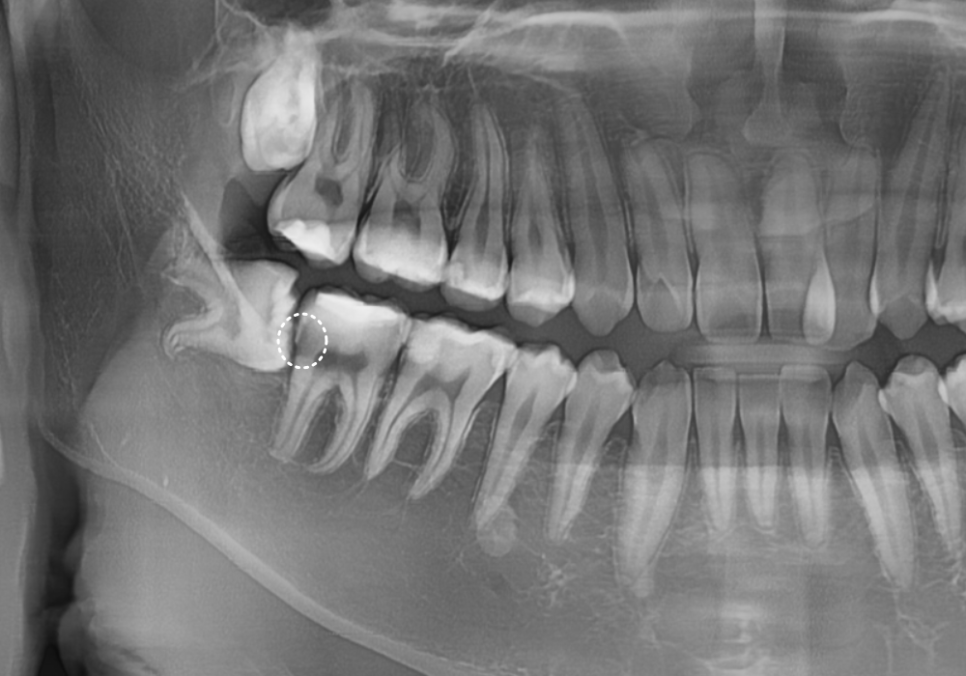

하지만, 진짜 문제는

사랑니를 뽑고 나서 드러났습니다.

221231

그동안 사랑니에 가려져 보이지 않던

앞 치아의 뒷면이 새까맣게 썩어 있었거든요.

사랑니가 찰싹 붙어있던 자리에

음식물 찌꺼기들이 쌓이면서,

앞 치아의 옆구리가 야금야금 썩어 들어간 거죠.

씹는 면이 아닌,

치아 옆면이기 때문에 잇몸에 가려져 있어서

그동안 발견하기가 참 어려웠을 거예요.

이 인접면 충치가 무서운 이유는

크게 두 가지입니다.

첫째, 발견이 매우 어렵습니다.

충치가 치아의 씹는 면이 아니라 옆구리,

그것도 잇몸 깊은 곳에서 시작되기 때문에

눈으로는 절대 보이지 않습니다.

엑스레이를 찍어도

사랑니에 가려져 있으면

충치 크기를 정확히 가늠하기 힘들죠.